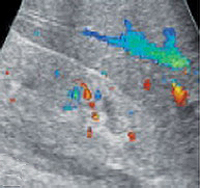

- УЗИ с допплерографией позволяет изучить кровообращение в почечных сосудах.

При проведении пробы Зимницкого выявляется изогипостенурия. УЗИ почек свидетельствует о снижении толщины паренхимы и уменьшении размера почек. Снижение внутриорганного и магистрального почечного кровотока выявляется на УЗДГ сосудов почек. Рентгенконтрастную урографию следует применять с осторожностью из-за нефротоксичности многих контрастных препаратов. Перечень других диагностических процедур определяется характером патологии, ставшей причиной развития ХПН.